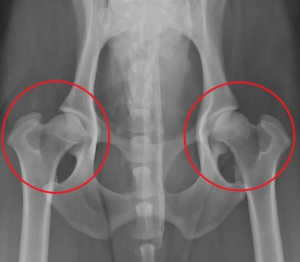

下は股関節の進行した変形性関節症のレントゲン写真です。赤丸の中が股関節ですが、大腿骨頭は変形して、関節内には骨棘の形成がみられます。同じ部位の正常写真が右です。